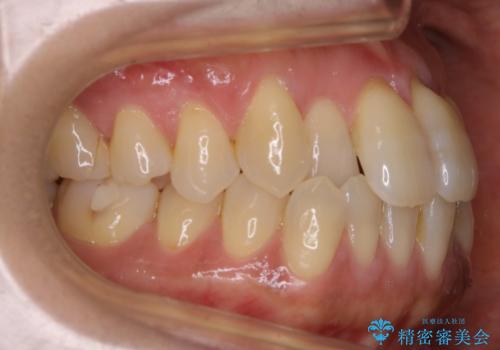

【非抜歯】短期間で実現する前歯の反対咬合治療

- 前歯のガタつきを主訴に来院されました。

奥歯の噛み合わせにはほとんど問題が見られず、歯列拡大とIPRのみの必要最低限の移動で歯並びの治療を計画することとなりました。